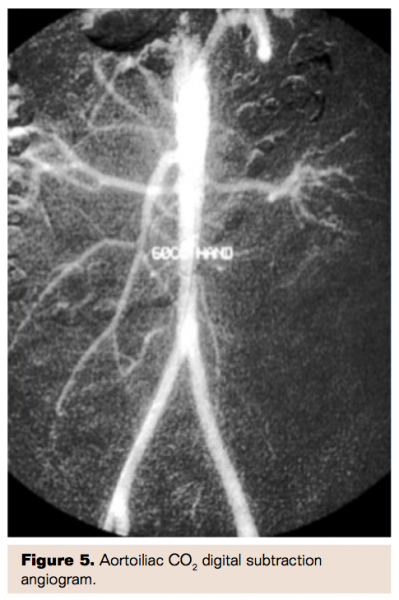

Carbon Dioxide Angiography

Without doubt the best way to avoid contrast nephropathy is simply not to administer any contrast. This has historically been possible using CO2 angiography13 but early systems were somewhat difficult to use, potentially dangerous to patients in the event of a mishap, and required use of large, bulky CO2 tanks. More recently, very portable, commercially available systems (Co2mmander, Portable Medical Devices) have been developed in which a very small canister of liquid carbon dioxide allows instantaneous conversion of liquid to gaseous CO2 that is easily administered using a double syringe system with a four-way stopcock (Figure 4). Many centers have adopted this system with highly satisfactory results and no patient safety issues. Angiographic images are of high quality for large vessels including aortoiliac studies as well as vessels as small as tibial and even pedal vessels (Figures 5-8). Placement of catheters as distally as possible in the circulation allows optimal imaging of smaller, distal vessels. Angiographic visualization has proven adequate for interventional procedures as well. The risk of contrast nephropathy is virtually zero, the cost of CO2 is extremely low, and there is no risk of contrast allergy further enhancing the safety profile of this approach.

Randomized studies have proven that there is no benefit to “benign” strategies such as the use of NAC and/or intravenous sodium bicarbonate. These approaches likely should be abandoned, just as use of intravenous fenoldopam was discontinued following the CONTRAST trial. Newer approaches such as the delivery of intrarenal fenoldopam using a specialized Benephit catheter should be considered although randomized trials are needed before this can be more widely adopted as standard of care. Finally, newer systems that facilitate the simple use of CO2 angiography should be utilized for peripheral procedures below the level of the diaphragm in patients at high risk of contrast nephropathy.